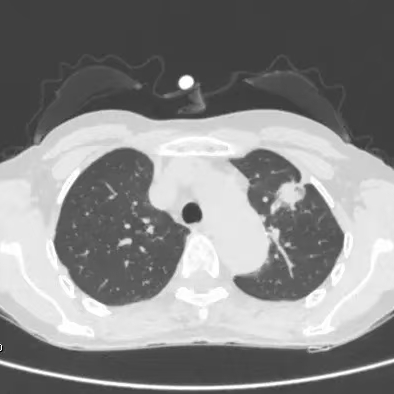

健康直通车: 健康是生命的宝贵财富,也是幸福生活的基石。为了更好地服务广大百姓,传播健康知识,葫芦岛市第二人民医院推出“健康直通车”专题栏目,将专业的医学知识以通俗易懂的方式传递给每一位市民,掌握科学的疾病预防方法,共同构筑健康中国的坚实基石。 什么是肺结节 肺结节是指肺内直径小于或等于3cm的类圆形或不规则形病灶,影像学表现为密度增高的阴影。大于3cm的称肿块。肺结节依其密度不同可分为实性结节、部分实性结节、磨玻璃结节,其中部分实性结节的恶性可能性最大,磨玻璃结节次之,实性结节尤其是小的实性结节结节最可能是良性的。 肺结节的常见病因 1、良性(约90%) 🔸 感染:结核、真菌、细菌性肺炎后遗留的瘢痕; 🔸 非感染:错构瘤(良性肿瘤)、炎性假瘤、血管瘤等。 2、恶性(约10%) 🔸原发性肺癌(如腺癌、鳞癌); 🔸转移性肿瘤(其他器官癌症转移至肺)。 如何根据影像判断肺结节性质 1、依据结节大小判断 🔸小于0.5cm的肺结节绝大多数都是良性的,属于微小结节。即使部分小于0.5cm肺结节是恶性的,但是适当的观察不影响预后。每年复查一次胸部CT就可以。 🔸大于0.5cm持续存在的纯磨玻璃结节,观察6个月,若持续存在,不管有无进展均多数是恶性的,视患者意愿,手术可以立即做也可观察至进展再做,不影响预后。 🔸大于0.8cm的部分实性结节恶性可能性非常大,应积极评估结节边缘毛刺、分叶、胸膜凹陷等征象。 🔸若实性部分大于0.5cm,恶性率显著提高。若在3~6个月随访期间实性部分增大或者总体部分增大,都可以考虑手术切除。而即使小于0.8cm的部分实性结节也需3个月就复查对比。 2、依据肺结节形态 如CT上提示病灶形态不规则、毛刺、分叶、胸膜凹陷、空泡征、血管集束征等,符合恶性肿瘤的征象。 🔸结节与正常肺组织之间界限非常清楚的恶性可能性大。 🔸结节密度不均呈混杂密度或均匀较大纯磨玻璃结节也基本是恶性的。 🔸有胸膜牵拉(不管是肺表面的脏层胸膜还是叶间裂部位的胸膜)的恶性可能性大。 🔸结节有浅分叶、细毛刺,密度较高而与周围肺组织边界不清的恶性可能性大。 🔸磨玻璃或混合磨玻璃结节存在小空洞的恶性可能性大。 🔸影像上似慢性炎表现,而没有炎症相关的其他异常,特别当所谓炎症区域内部或一侧与正常肺组织之间界限非常清楚的基本上是恶性的。 3、从结节发展情况来看 所有随访中增大进展的都需要考虑恶性可能,不进展而持续存在的纯磨玻璃结节也需考虑恶性。 葫芦岛市第二人民医院肺结节诊治中心孙振教授深耕肺结节领域四十余载,凭借对临床实践的执着钻研与深厚积淀,在肺结节精准诊断及鉴别诊断领域形成独到见解。他系统总结海量临床病例,创新性提炼出一套科学化、规范化的肺结节全周期诊疗体系,尤其在早期微小结节的影像特征识别、良恶性风险分层等方面积累了丰富经验,为众多患者提供了精准、高效的诊疗方案。 人民医院·人民名医 孙振 主任医师 三级教授 ·葫芦岛市第二人民医院胸外科主任、肺结节诊治中心主任 ·中国医科大学客座教授 ·原央企总医院著名胸外科专家 ·辽宁省医学会胸外科委员 ·辽宁省抗癌协会肺癌专业委员会委员 ·辽宁省细胞生物学学会食管癌专业委员会理事 ·主持多项科研成果获科技成果奖、科技进步奖、国家专科奖项 医学成就 从事胸外科临床工作近40年,担任胸外科首席专家及科室主任20余年,是我省胸外科领军人物,推动肺癌、食管癌等胸部肿瘤外科的规范化诊疗,在央企总医院牵头成立了肺结节诊疗中心,率先开展CT引导下肺内小结节定位切除,既确切完整切除肺内小结节,又降低肺功能损害。 专业特色 擅长肺癌、食管癌的外科手术和综合治疗,在各类高难度胸外伤手术治疗、胸腔镜微创手术、胸腺瘤手术及复杂并发症处理方面具有高深造诣,尤其擅长肺癌早期诊断,胸部小结节CT早期肺癌的鉴别等。完成各类高难度胸外科手术5000余例,其中微创手术占比达90%,治愈率达98%,多项业务填补省内空白。 开展的高难手术 胸腔镜肺部结节微创手术、肺癌根治术、食管癌根治术、各种纵隔肿瘤切除术、胸骨后甲状腺手术及胸部复合性外伤的抢救手术等。